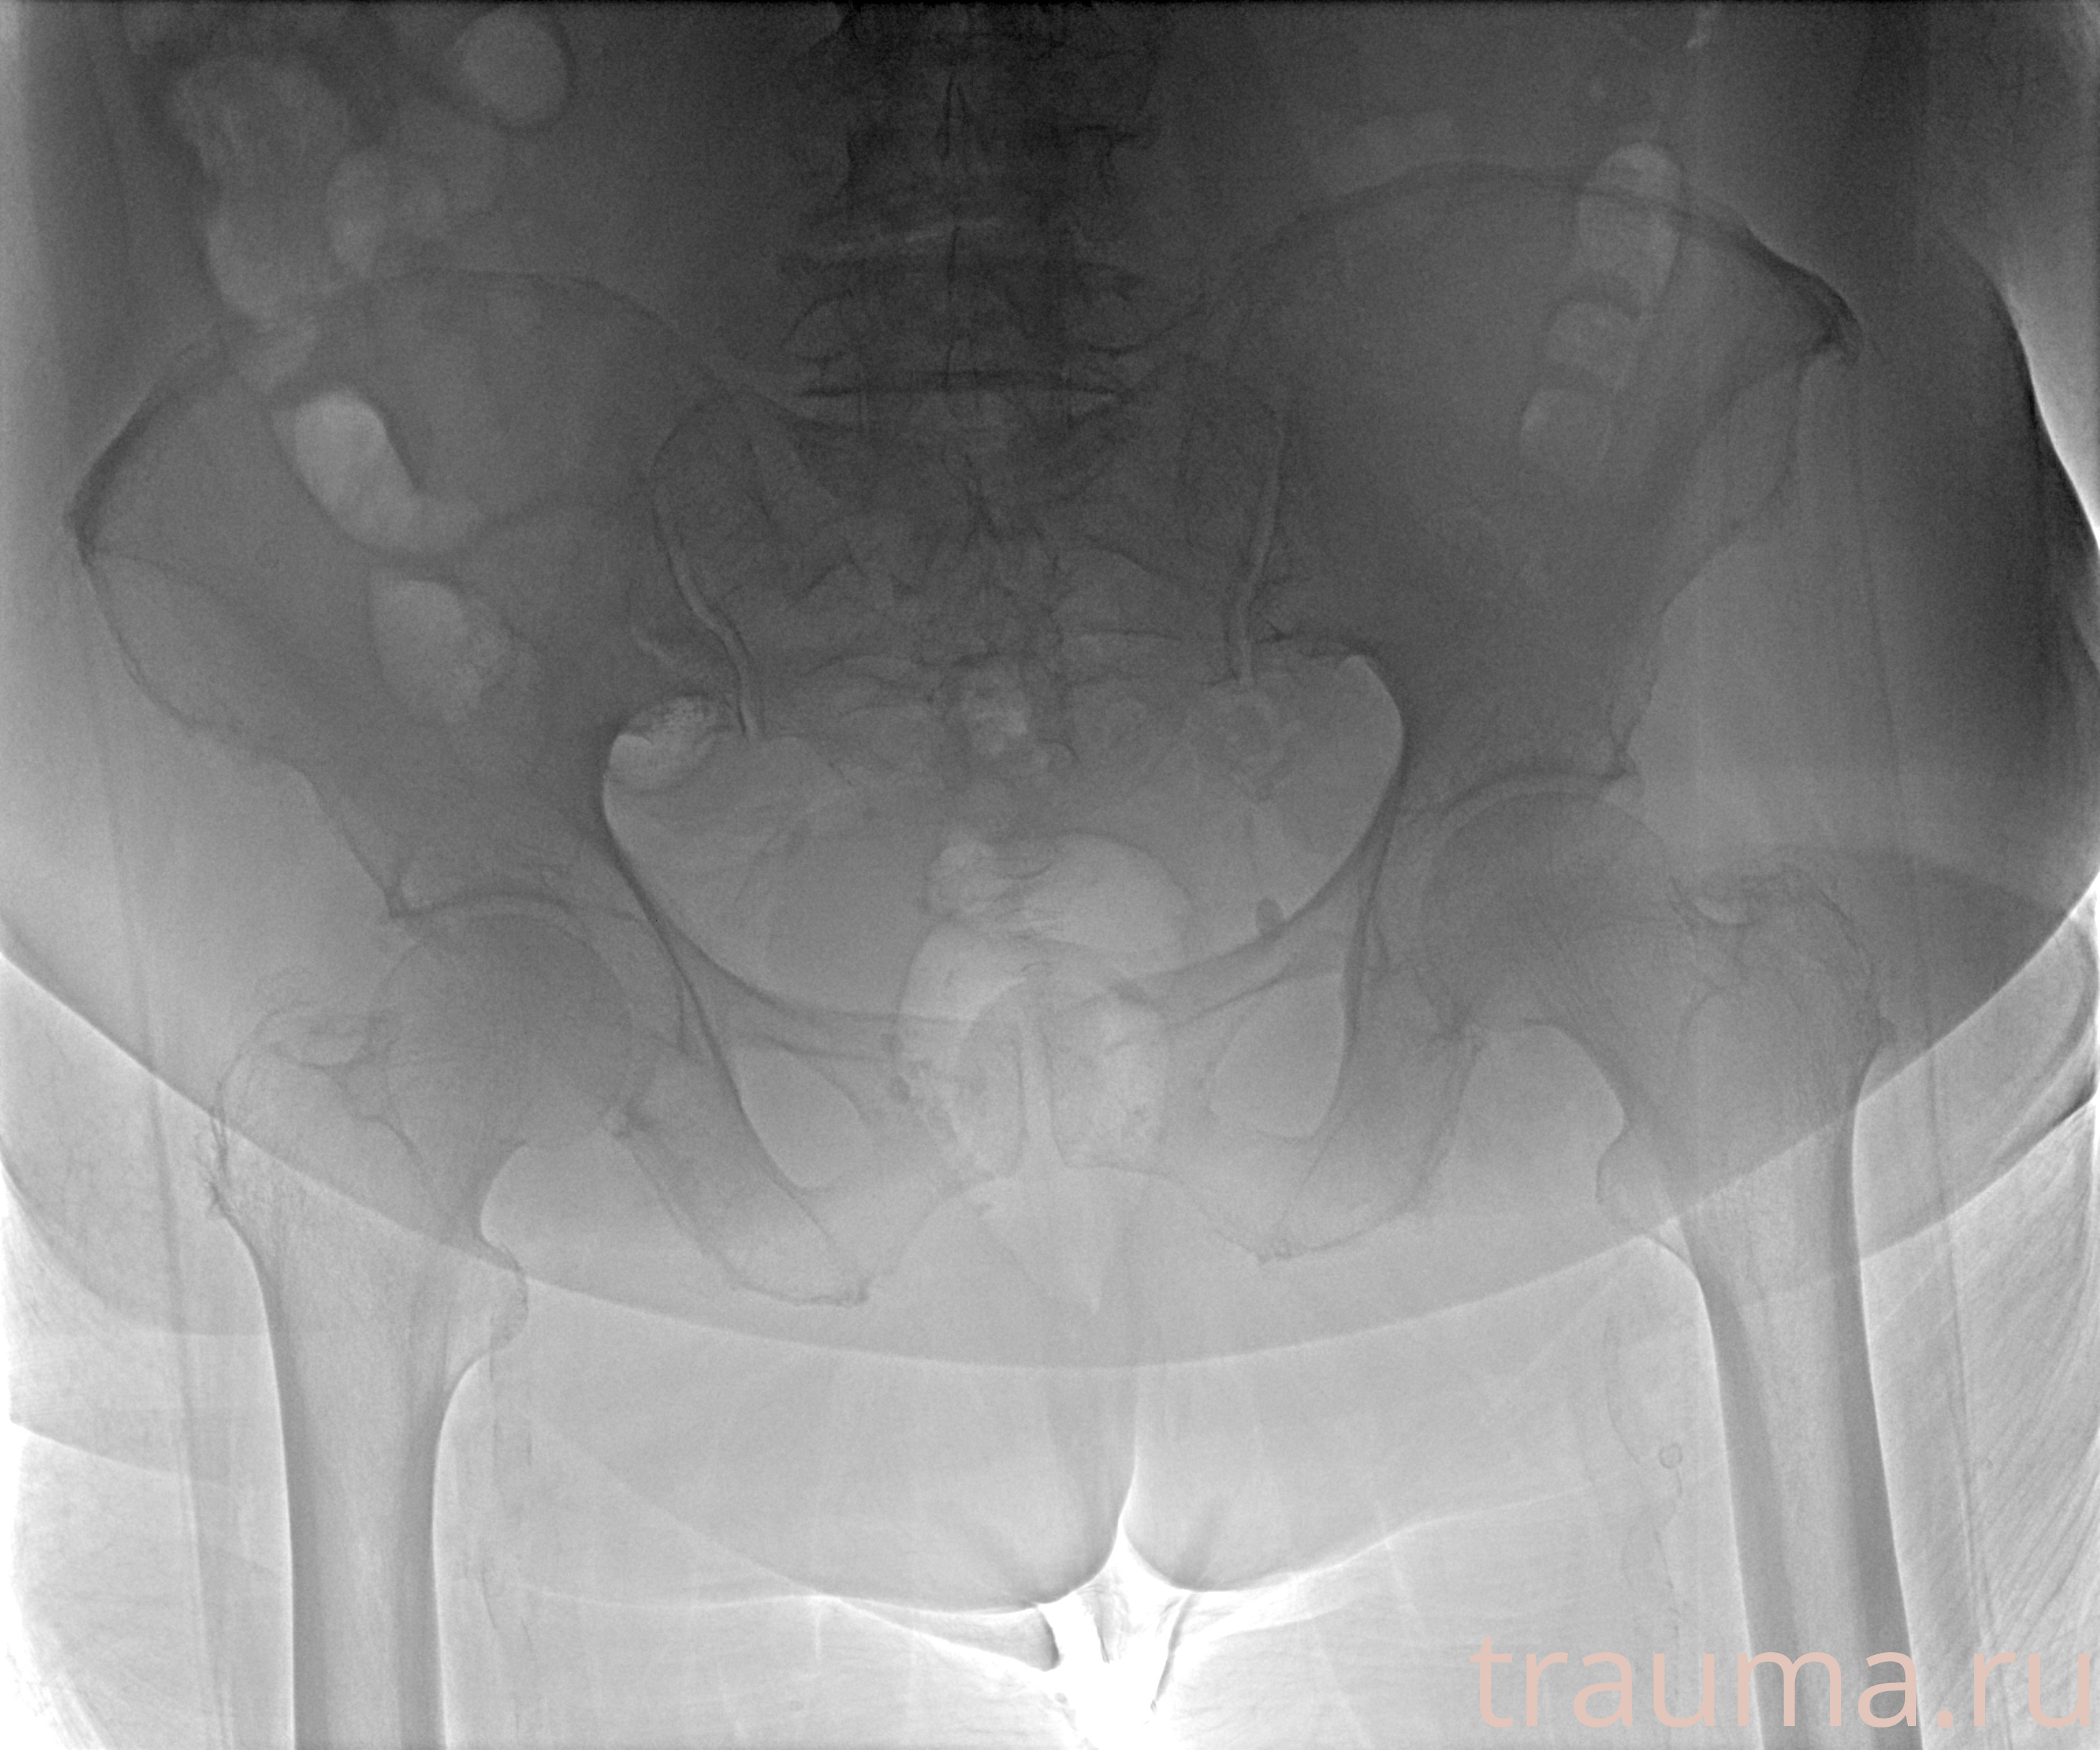

Рентген на дому: по вашему адресу приезжает врач-рентгенолог, травматолог-ортопед с мобильным рентгеновским аппаратом, проводит диагностику травмы или заболевания, делает необходимые рентгенограммы, дает рекомендации по дальнейшему лечению. Получить качественные снимки в домашних условиях возможно благодаря уникальной методике, разработанной МосРентген Центром для института  Склифосовского